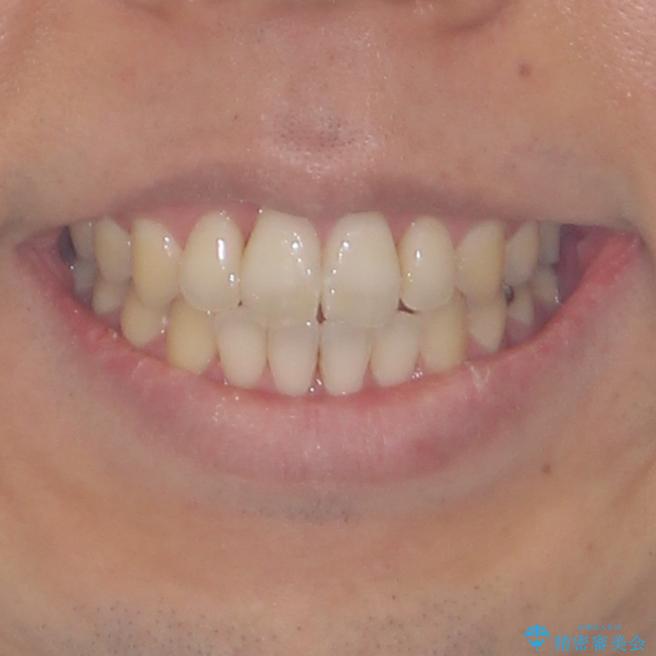

- 前歯のデコボコと、上顎前歯の突出感を気にして来院された患者様です。

通常の咬み合わせ位置と比較して、上顎の歯列が全体的に前方にある状態で、上下前歯の前後方向の位置に著しい差がありました。

上顎歯列全体を後方に移動させたため、口元の突出感も改善され、装置を外してからは口が閉じやすくなりました。